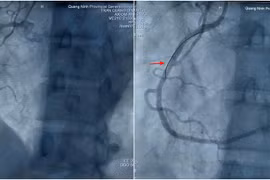

Các bác sĩ Bệnh viện Đa khoa tỉnh Quảng Ninh đã kịp thời can thiệp đặt stent, cứu sống bệnh nhân nhồi máu cơ tim đột ngột sau phẫu thuật nội soi.